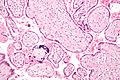

Pogreška pri izradbi sličice:

Mikrograf infekcije citomegalovirusom. Na donjem desnom dijelu slike mogu se vidjeti stanice velikih jezgara karakteristične za ovu infekciju.